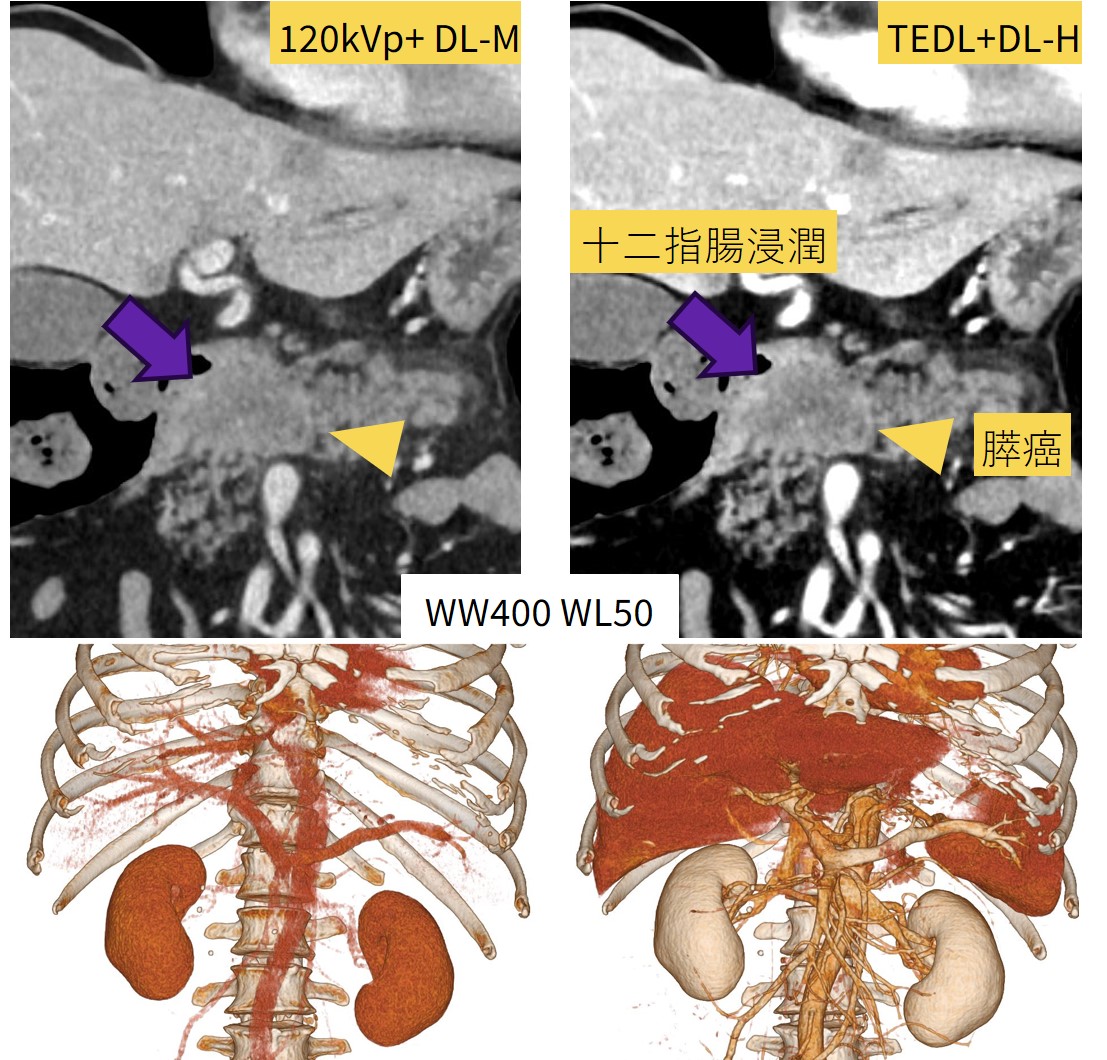

~高体重症例~

膵腫瘍・肝腫瘍疑いで紹介され精査のためDynamic CTを撮影。体重100kg、BMI34.7と高く、造影剤量が足りず本来の必要量の7割までしか注入できなかった症例です。

120kVpでも病変検出は可能ですが、TEDLを使用したことで正常部位とのコントラストが上昇し、視認性が上がり検出は120kVpよりも容易となっており、膵癌が十二指腸まで浸潤していることも分かりやすくなっています。また、TEDLを使用することでVR像の作成も十分に可能でした。

Fig7. 高体重症例で造影剤が不足した場合でも、TEDL・TFDLを用いることで

コントラスト、ノイズ低減で十分な画質が得られた症例